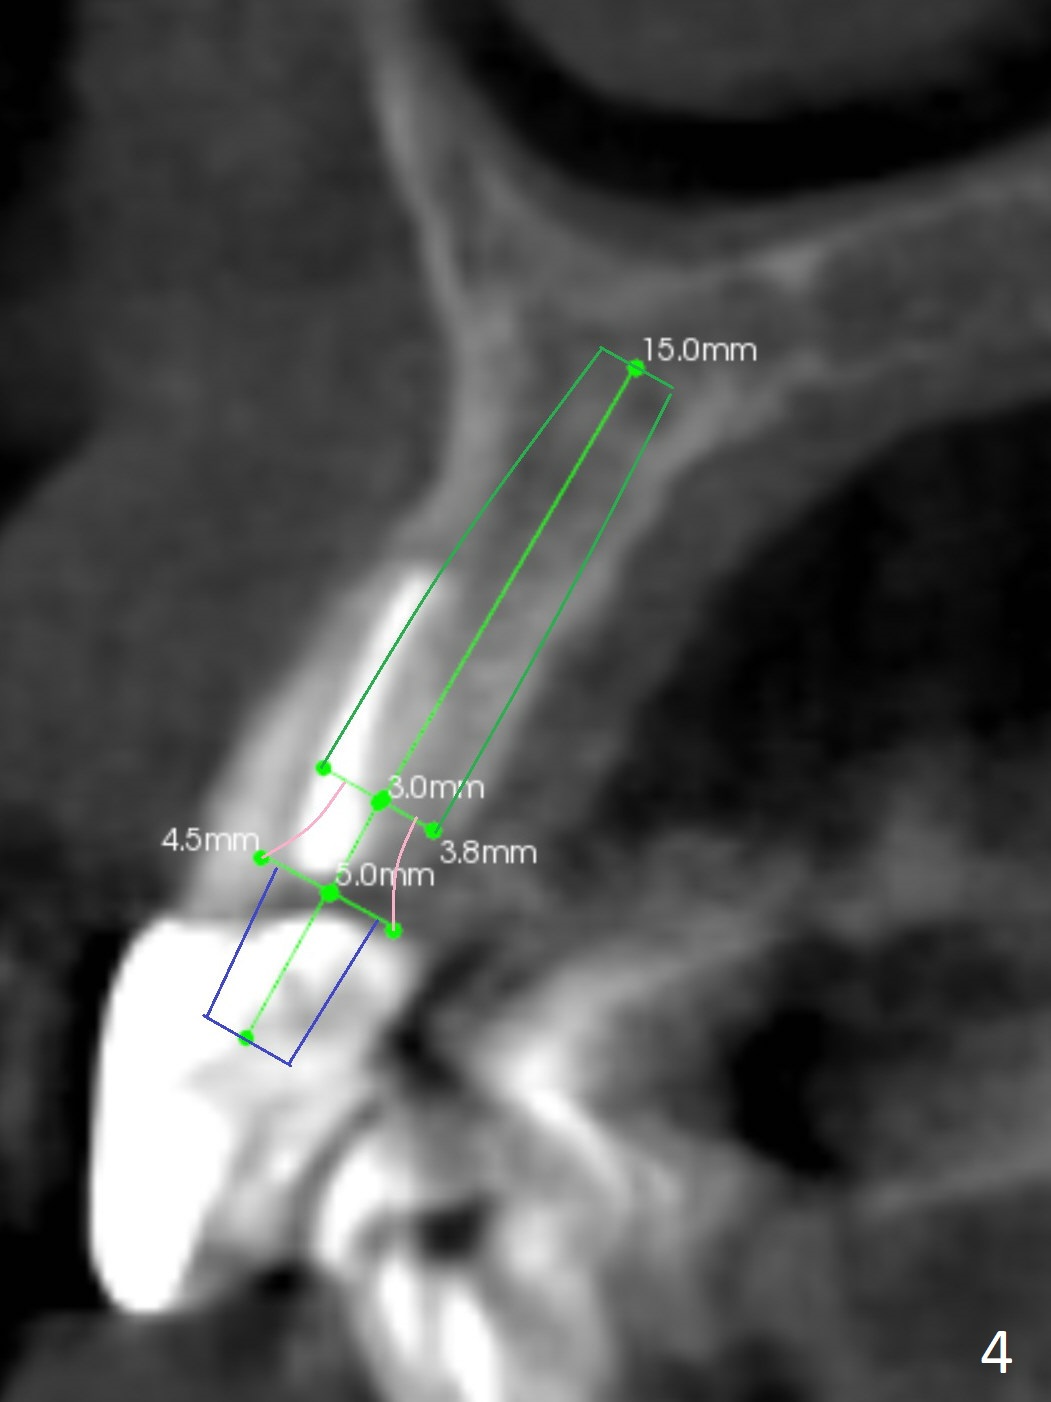

A 60-year-old man fractures the tooth #10 after implant at #7 (Fig.1). An implant should be placed in the middle of the socket at #10 since there is periapical radiolucencey at #9 and 11 (Fig.2 CBCT). The buccal plate at #10 is thin (Fig.4). A 3.8x15 mm implant (the smallest 2-piece) appears to be large for the alveolus (Fig.5). The gingiva must be thin as well. This is called thin biotype. In fact the buccal plate seems to have undergone bone resorption post 3.8x15 mm implant placement at #7. Therefore a 2.5 or 3x14 or 16 mm 1-piece implant will be placed at #10 (Fig.5). Also prepare angled ones. Take photos of #7 and 10 to show bone resorption and the thin gingiva. If the caries is not extensive, perform socket shield. In fact a 1-piece implant is chosen because of the narrow mesiodistal space.